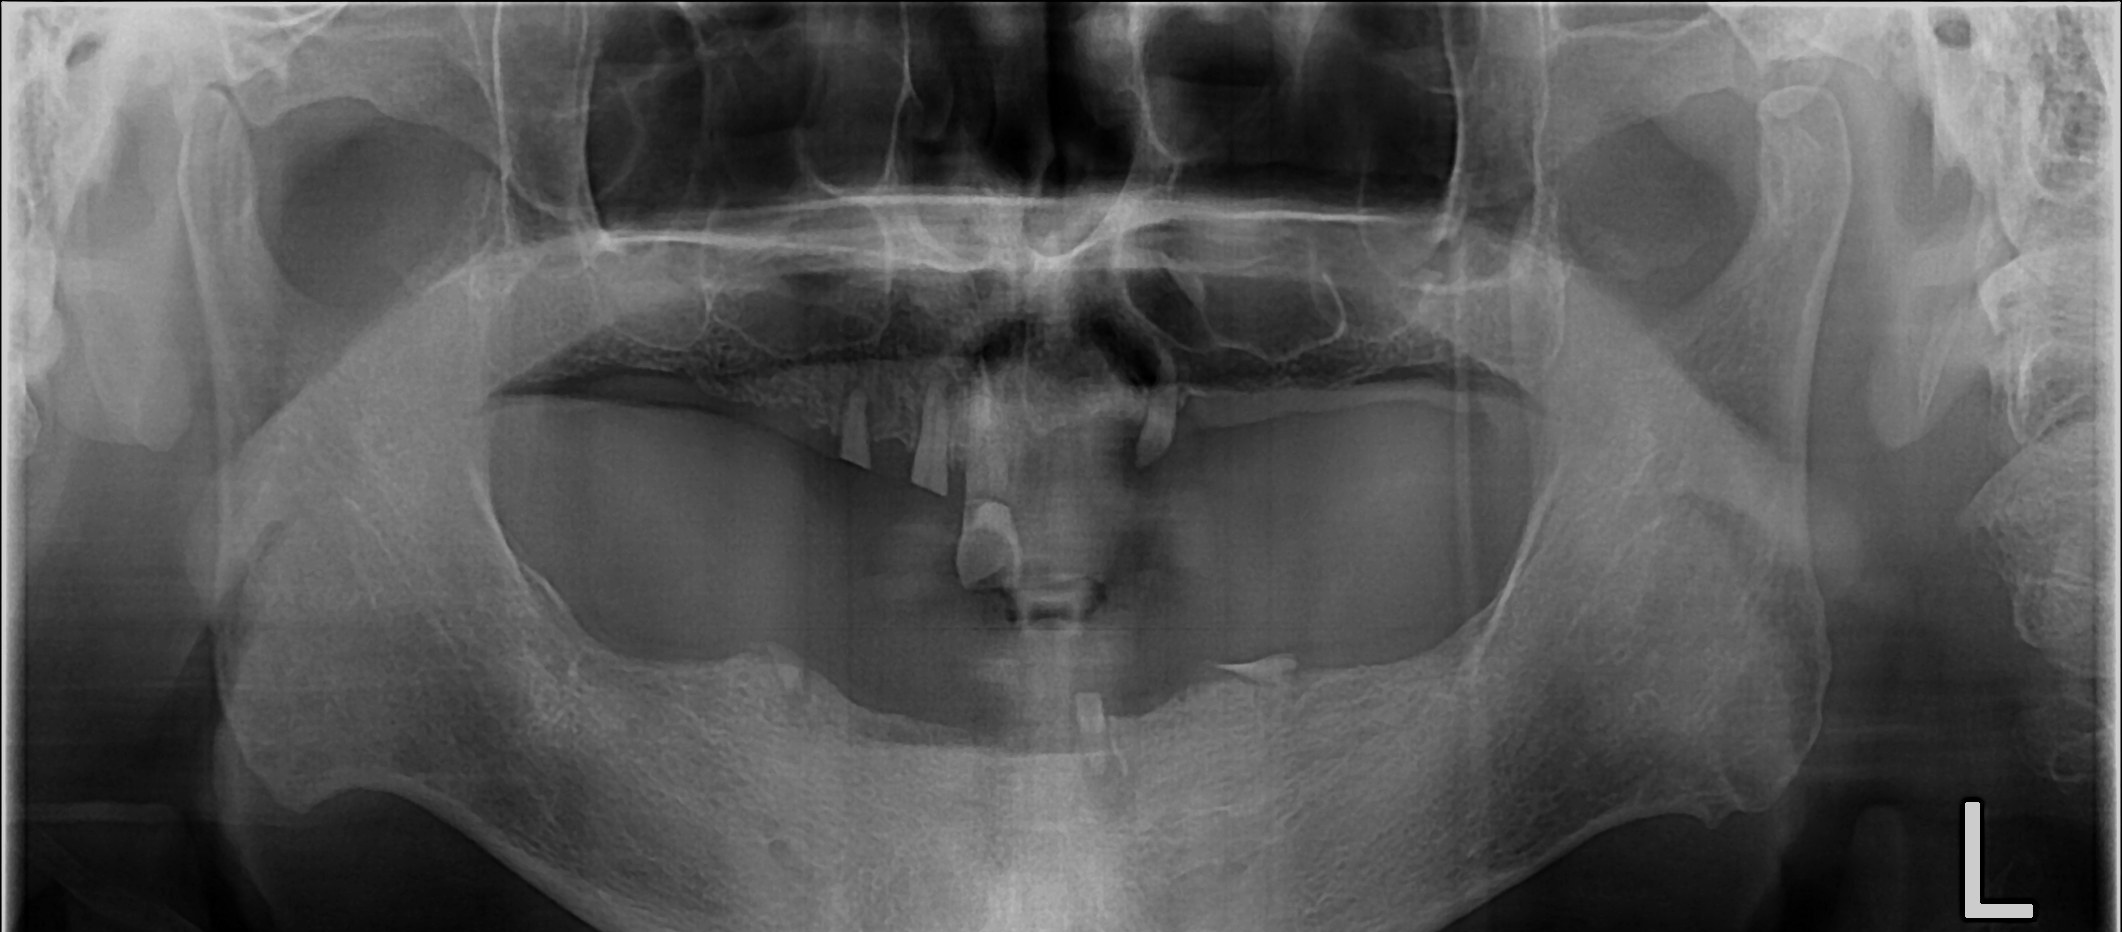

Before